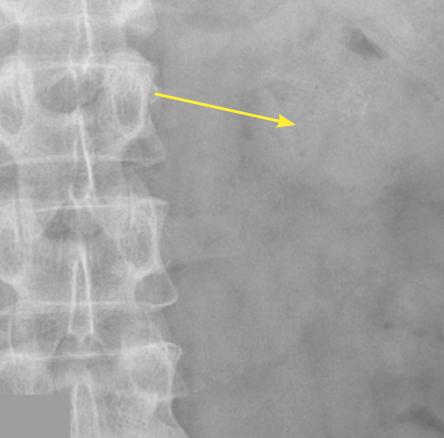

Lors de son hospitalisation, un scanner abdominal permet de localiser avec précision un calcul caliciel rénal radio-opaque gauche de 6 × 8 mm, de faible densité (354 UH), sans dilatation calicielle (fig. 1). En corrélation avec la lecture du scanner, le pourtour du calcul est difficilement visualisé sur la radiographie de l’abdomen sans préparation (fig. 2).